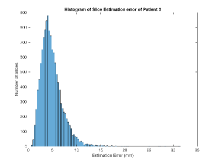

Exp. 3: Adult thorax data: To show the versatility of our approach we also apply it to adult thorax scans. For this experiment no organ specific training is performed but the whole volume is used. We evaluate reconstruction performance similar to Exp. 1 and prediction performance when is projected on an external plane, comparable to X-Ray examination using C-Arms. The latter provides insights about our method’s performance when applied to interventional settings in contrast to motion compensation problems. 60 healthy adult thorax scans were randomly selected, 51 scans used for and nine scans used for . Each scan is intensity normalised and resampled in a volume of with spacing . Using the Fibonacci sampling method, 25 sampling plane of size , evenly spaced between -50 and +50, were rotated over 500 normals. Training took approximately 20 hours for 60 epochs. Fig. 4c shows an example reconstruction result gaining 28dB PSNR with additional SVR. prediction takes approx. 20 ms/slice for this data.

Here we show for Exp. 1, Exp. 2, and Exp. 3 randomly selected examples of images that have been presented to the network (ground truth) compared to an image sampled at the predicted location.

In these experiments, we present a ground truth (GT) image to the network to estimate the respective transformation parameters needed to reorient the slice in its correct world co-ordinates. Using the transformation parameters, we generated a slice from the 3D atlas in the location where the network has predicted that slice should be (denoted as SVRNet).

The slices are compared side-by-side to give a visual representation of “where the slice really is” and “where the network thinks the slice is”.

0..5.3 Exp. 3:

We replicated the experiment on adult thorax data without specifically segmented organs. This approach was applied to CT acquisition, shown in Fig 13 and 14, as well as Digitally Reconstructed Radiographs generated using Siddon-Jacobs Ray Tracing shown in Fig. 16.